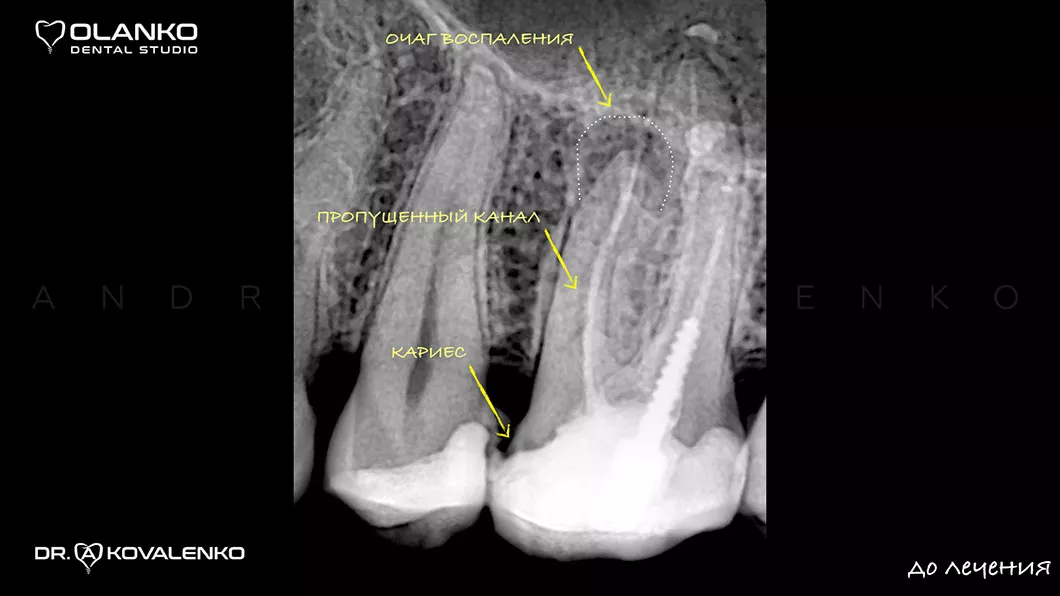

Лечение корневых каналов зуба с использованием микроскопа, на сегодняшний день, является золотым стандартом мировой стоматологической практики. Сложная система корневых каналов в зубе имеет очень малый диаметр и индивидуальную анатомию, поэтому врач, работающий без увеличения, не может качественно очистить и найти все корневые каналы на ощупь.

На примере перелечивания корневых каналов верхнего жевательного зуба

Мы имеем огромный клинический опыт лечения зубов со сложной анатомией (искривлёнными, склерозированными каналами), а также повторного перелечивания каналов с кистами, гранулемами, сломанными инструментами, с последующими отличными результатами заживления очагов хронического воспаления.